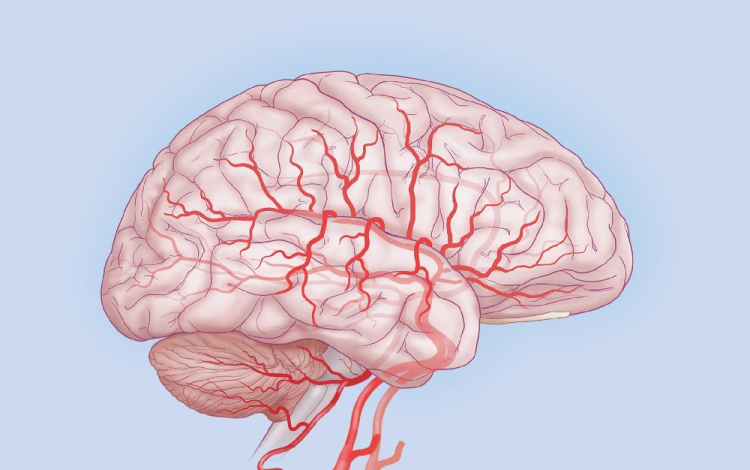

A Stanford Egyetem kutatói rohamok során jelentkező agyi aktivitást konvertáltak zenévé.

Dr. Josef Parvizi neurológus és Chris Chafe professzor, zenekutató mintegy száz elektróda segítségével regisztrálta a rohamok során keletkező agyi aktivitást, és a mintázatot zenévé alakították át. Az egyes hullámokhoz az emberi hangtartományhoz közeli hangjegyeket rendelve jutottak el az agy zenéjéig.

A módszer során a hagyományos módszert jelentő eeg-vel térképezték fel a normál aktivitás, illetve a görcsroham során jelentkező elektromos hullámokat, melyek az idegsejtek kisülése miatt jönnek létre.

A módszer jelentősége túlmutathat egy érdekes kutatáson, ugyanis az így kapott hallgatózási lelet alapján könnyűszerrel el lehet különíteni a rohamos aktivitást a normál működésre jellemzőtől. A kutatók szerint az „agyi sztetoszkóp” az epilepsziás betegek diagnosztikájában jelent pontosabb alternatívát. A fejlesztés az egyetem Bio-X Interdiszciplináris Programjának keretein belül zajlott, mely 2000 óta fut, és mintegy 141 tudóst foglalkoztat.